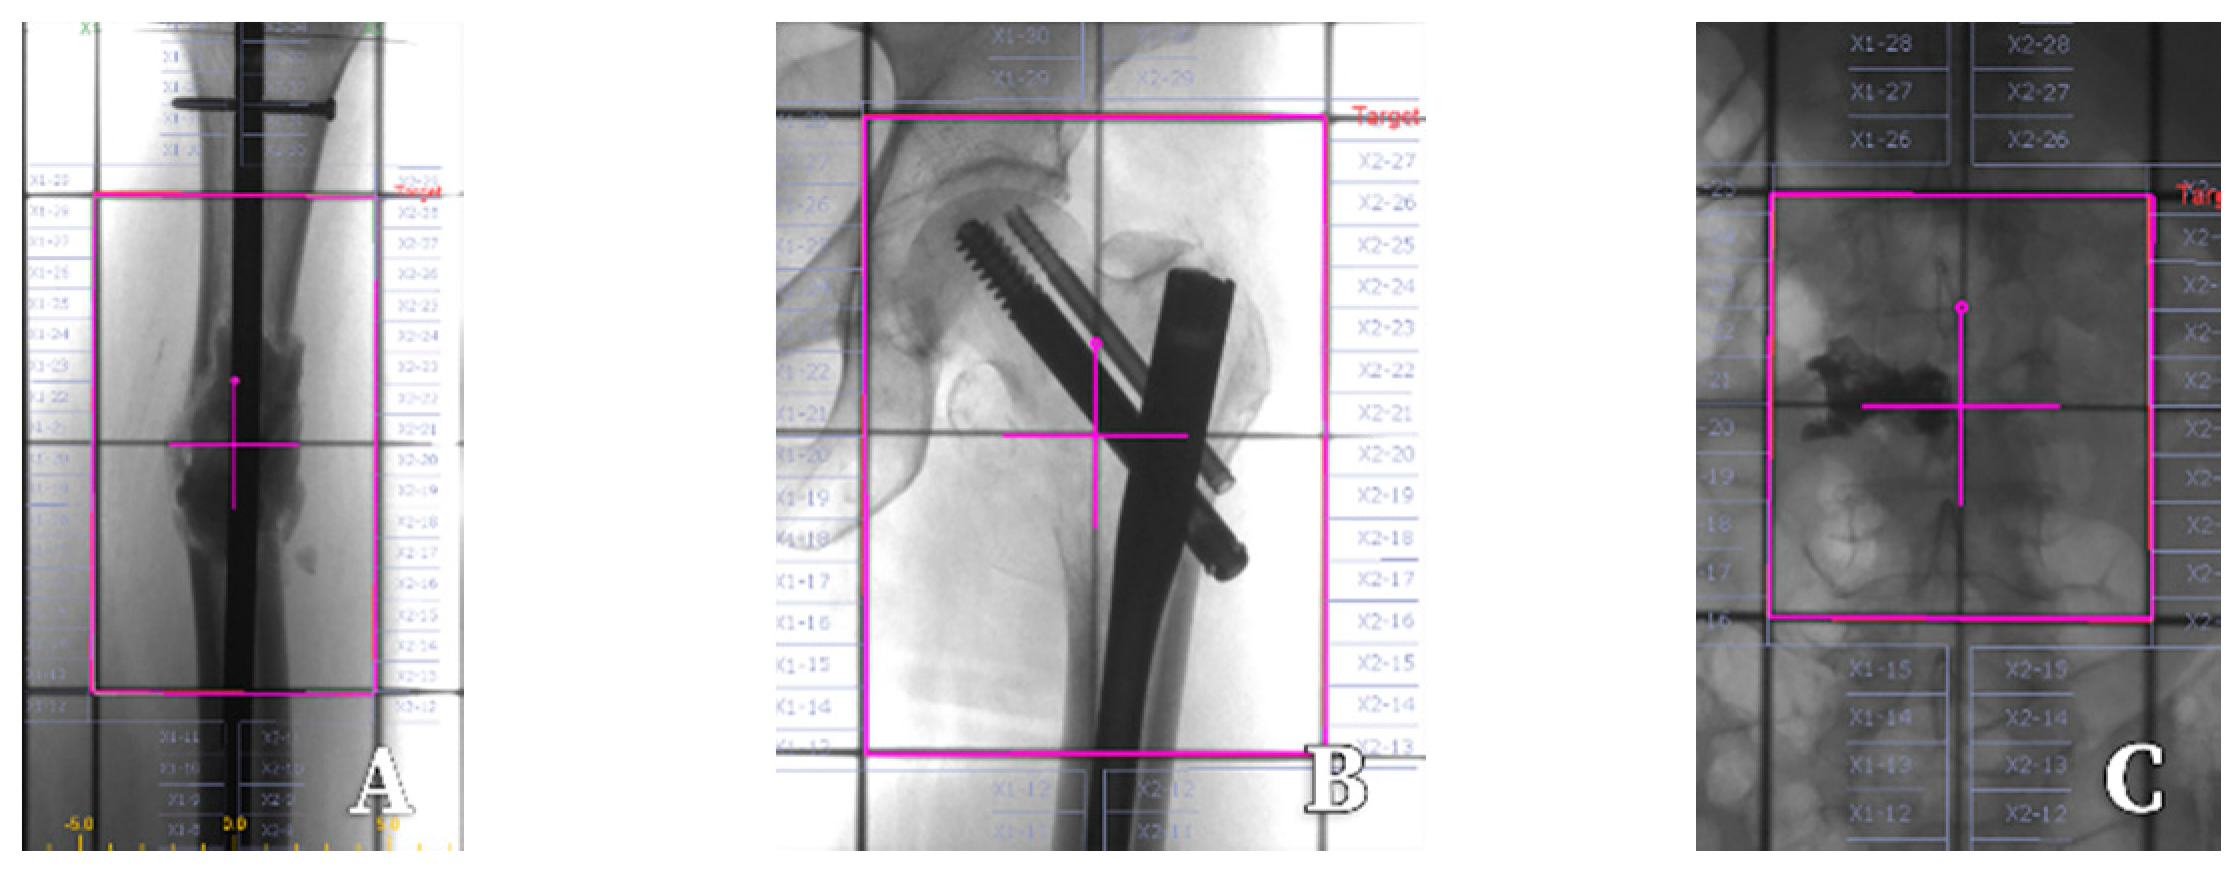

- Li, T.; Li, J.; Wang, Z.; Liu, B.; Han, D.; Wang, P. A preliminary comparative clinical study of vertebroplasty with multineedle or single-needle interstitial implantation of 125I seeds in the treatment of osteolytic metastatic vertebral tumors. J. Neurosurg. Spine 2014, 20, 430–435. [Google Scholar] [CrossRef] [PubMed]

- Qian, J.; Bao, Z.; Zou, J.; Yang, H. Effect of pedicle fixation combined with 125I seed implantation for metastatic thoracolumbar tumors. J. Pain Res. 2016, 9, 271–278. [Google Scholar] [PubMed]